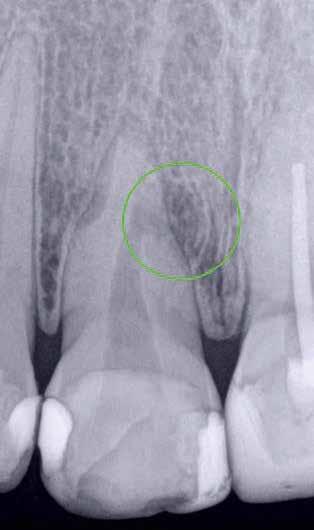

1. ábra: Kiindulási röntgenfelvétel. – 2. a–c. ábra: A horizontális irányú metszeten kiterjedt csontpusztulás jelei láthatóak (a), a vertikális irányú metszeteken mindkét középső metszőfognak megfelelően észlelhető a csontpusztulás (b–c).

Egy fiatal hölgy, aki modellként dolgozik és emiatt nagy jelentőséget tulajdonít a saját fogai megőrzésének, a két középső alsó metszőfoga alatt kialakult duzzanat miatt kereste fel a rendelőnket. Vizsgálatot követően megállapítottuk, hogy a fogak mellett 20 mm szélességű tasak van jelen, amely az egyik alsó középső metszőfog disztális oldalától a másik alsó középső metszőfog disztális felszínéig terjed. Ebből az következik, hogy ezen a területen a teljes bukkális kortikális csontlemez leépült. Mindkét fog III. fokú mobilitással rendelkezett, amely tovább rontotta a kérdéses fogak várható prognózisát. Szenzibilitásvizsgálatot is végeztünk. A két alsó középső metszőfog esetében a páciens nem jelzett hidegingert, de a többi fog esetében fiziológiás választ adott. Periapikális röntgenfelvétel készült, amelyen nem mutatkozott meg a vélelmezett elváltozás (1. ábra). Ennek megfelelően CBCT-felvételt készítettünk, hogy jobban meg tudjuk vizsgálni a kérdéses területet. Ezen a felvételen már láthatóvá vált a vertikális és horizontális irányú csontpusztulás tényleges mértéke. A horizontális síkban készített metszeten a két alsó középső metszőfog körül megfigyelhető volt a bukkális kortikális csontlemez és a szivacsos csontállomány hiánya. A defektus szélessége 14,11 mm, a mélysége pedig 6,28 mm volt (2. a. ábra). A vertikális irányú metszeten láthatóvá vált, hogy a középső metszőfogak gyökerének bukkális oldalát nem fedi csont, és ez a defektus már a gyökércsúcsok alatti területre is kiterjedt (2. b–c. ábra)